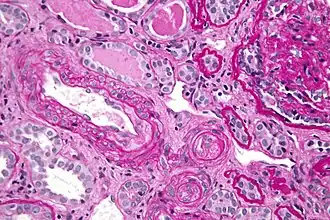

![]() Micrografía mostrando microangiopatía trombótica, una hallazgo histopatológico presente en las crisis hipertensivas. Biopsia de riñón teñida con ácido peryódico de Schiff | ||